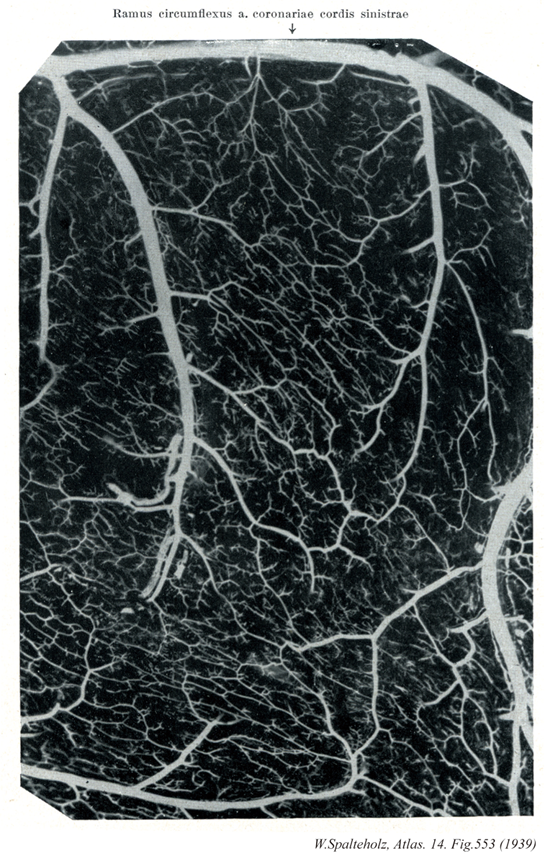

01【Circumflex branch of left coronary artery回旋枝(左冠状動脈の) Ramus circumflexus (Arteria coronaria sinistra)】 Continuation of the left coronary artery that travels in the left coronary sulcus. →(左冠状動脈の回旋枝は前室間枝とともに左冠状動脈の延長で左冠状溝を走る枝。冠状動脈内を左方、ついで下方にすすみ心房、心室に分布する。)